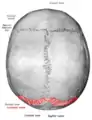

Lambdoid suture (shown in red line)